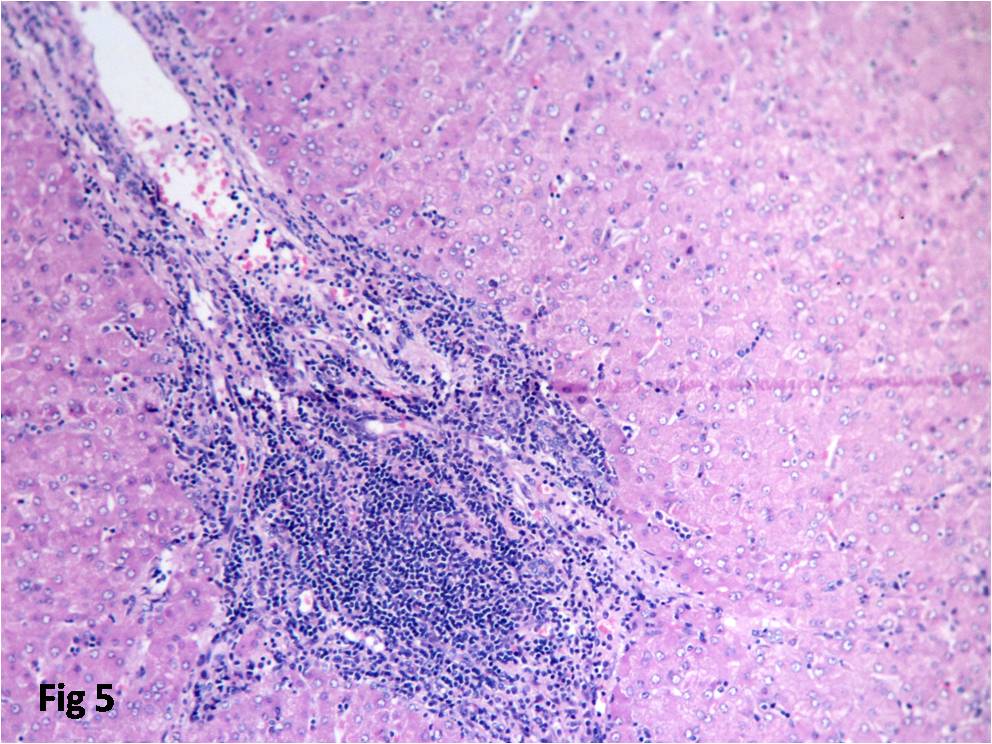

Follicular Lymphoma: A Clinicopathological Analysis from a Tertiary care Institute in Southern India